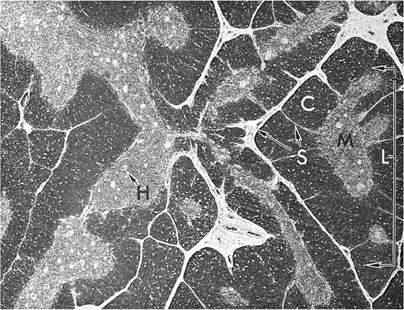

Figure 14.7. Histology of thymus shows lobules (L) consisting of cortex (C) and medulla (M). H, Hassall corpuscles; S, septa (trabeculae).